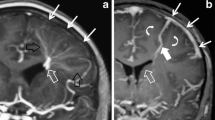

Venous infarction commonly leads to hemorrhagic complications, much more so than arterial infarction [10, 11]. In the setting of cerebral sinus venous thrombosis, hemorrhagic infarction (microhemorrhage) occurs in approximately 37% of venous infarcts and frank intracerebral hemorrhage (hemorrhage >1 cm) occurring in 21% of venous infarcts [11]. Parenchymal hemorrhage correlates with high venous pressure (>42 mmHg) and is hypothesized to arise from venule rupture and infarction [4]. Gradient echo and susceptibility-weighted imaging allow for sensitive, early detection of hemorrhage [3]. Figure 8 shows hemorrhage in the left temporal lobe of a neonate, suggesting vein of Labbe´ thrombosis.

A 2-week-old boy with congenital heart disease and new apnea with a vein of Labbé hemorrhagic infarct. a Axial CT image shows mixed attenuation hemorrhage in the left temporal lobe with adjacent edema. b A 3-D MR venography image shows absence of the left vein of Labbé (black arrow). Note the normal right vein of Labbé (white arrow)